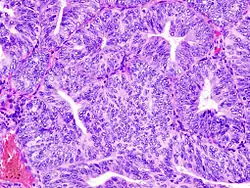

Endometrioid adenocarcinoma from biopsy. H&E stain. -

(A) proliferative endometrium (Left: HE × 400) and proliferative endometrial cells (Right: HE × 100)

(B) secretory endometrium (Left: HE × 10) and secretory endometrial cells (Right: HE × 10)

(C) atrophic endometrium (Left: HE × 10) and atrophic endometrial cells (Right: HE × 10)

(D) mixed endometrium (Left: HE × 10) and mixed endometrial cells (Right: HE × 10)

(E): endometrial atypical hyperplasia (Left: HE × 10) and endometrial atypical cells (Right: HE × 200)

(F) endometrial carcinoma (Left: HE × 400) and endometrial cancer cells (Right: HE × 400).